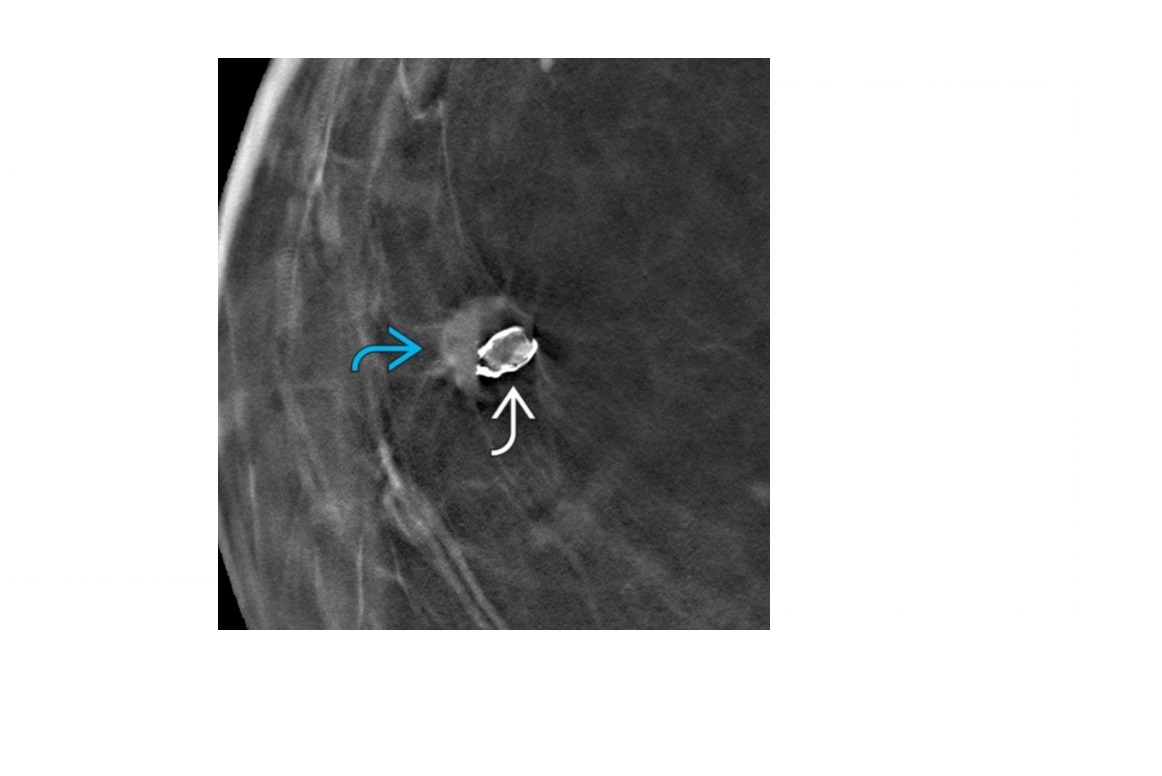

Features of oil cyst?

A

Fatty tissue necrosis

Acutely:

Superficial fluid collection with surrounding ↑ echogenicity due to edema on US

Oil cyst(s): Circumscribed lucent round mass ± rim Ca⁺⁺ on mammograph

‘Egg shell’ Calcification

MRI = shows central hyperintense fat on T1 and rim of peripheral enhancement